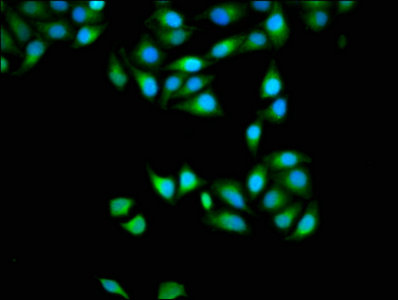

Immunofluorescence staining of Hela cells with CSB-PA846585LA01HU at 1:133, counter-stained with DAPI. The cells were fixed in 4% formaldehyde, permeabilized using 0.2% Triton X-100 and blocked in 10% normal Goat Serum. The cells were then incubated with the antibody overnight at 4°C. The secondary antibody was Alexa Fluor 488-congugated AffiniPure Goat Anti-Rabbit IgG(H+L).